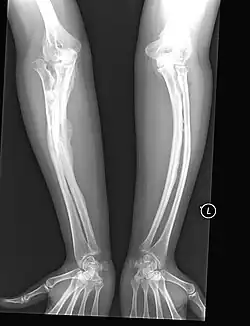

The main symptom of osteogenesis imperfecta is fragile, low mineral density bones; all types of OI have some bone involvement.[5] In moderate and especially severe OI, the long bones may be bowed, sometimes extremely so.[28] The weakness of the bones causes them to fracture easily—a study at the Endocrine Unit at the National Institute of Child Health in Karachi, Pakistan found an average of 5.8 fractures per year in untreated children.[29] Fractures typically occur much less after puberty, but begin to increase again in women after menopause and in men between the ages of 60 and 80.[1]: 486

OI type III causes osteopenic bones that fracture very easily, sometimes even in utero, often leading to hundreds of fractures during a lifetime;[24] early scoliosis that progresses until puberty; dwarfism (a final adult height frequently less than 4 feet or 120 centimetres); loose joints; and possible respiratory problems due to low rib cage volume causing low lung volumes.[5]: 1512

Diagnosis is typically based on medical imaging, including plain X-rays, and symptoms. In severe OI, signs on medical imaging include abnormalities in all extremities and the spine.[97] As X-rays are often insensitive to the comparatively smaller bone density loss associated with type I OI, DEXA scans may be needed.[5]: 1514

An OI diagnosis can be confirmed through DNA or collagen protein analysis, but in many cases, the occurrence of bone fractures with little trauma and the presence of other clinical features such as blue sclerae are sufficient for a diagnosis. A skin biopsy can be performed to determine the structure and quantity of type I collagen. While DNA testing can confirm the diagnosis, it cannot absolutely exclude it because not all mutations causing OI are yet known and/or tested for.[83]: 491–492 OI type II is often diagnosed by ultrasound during pregnancy, where already multiple fractures and other characteristic features may be visible. Relative to control, OI cortical bone shows increased porosity, canal diameter, and connectivity in micro-computed tomography.[98] OI can also be detected before birth by using an in vitro genetic testing technique such as amniocentresis.[99]